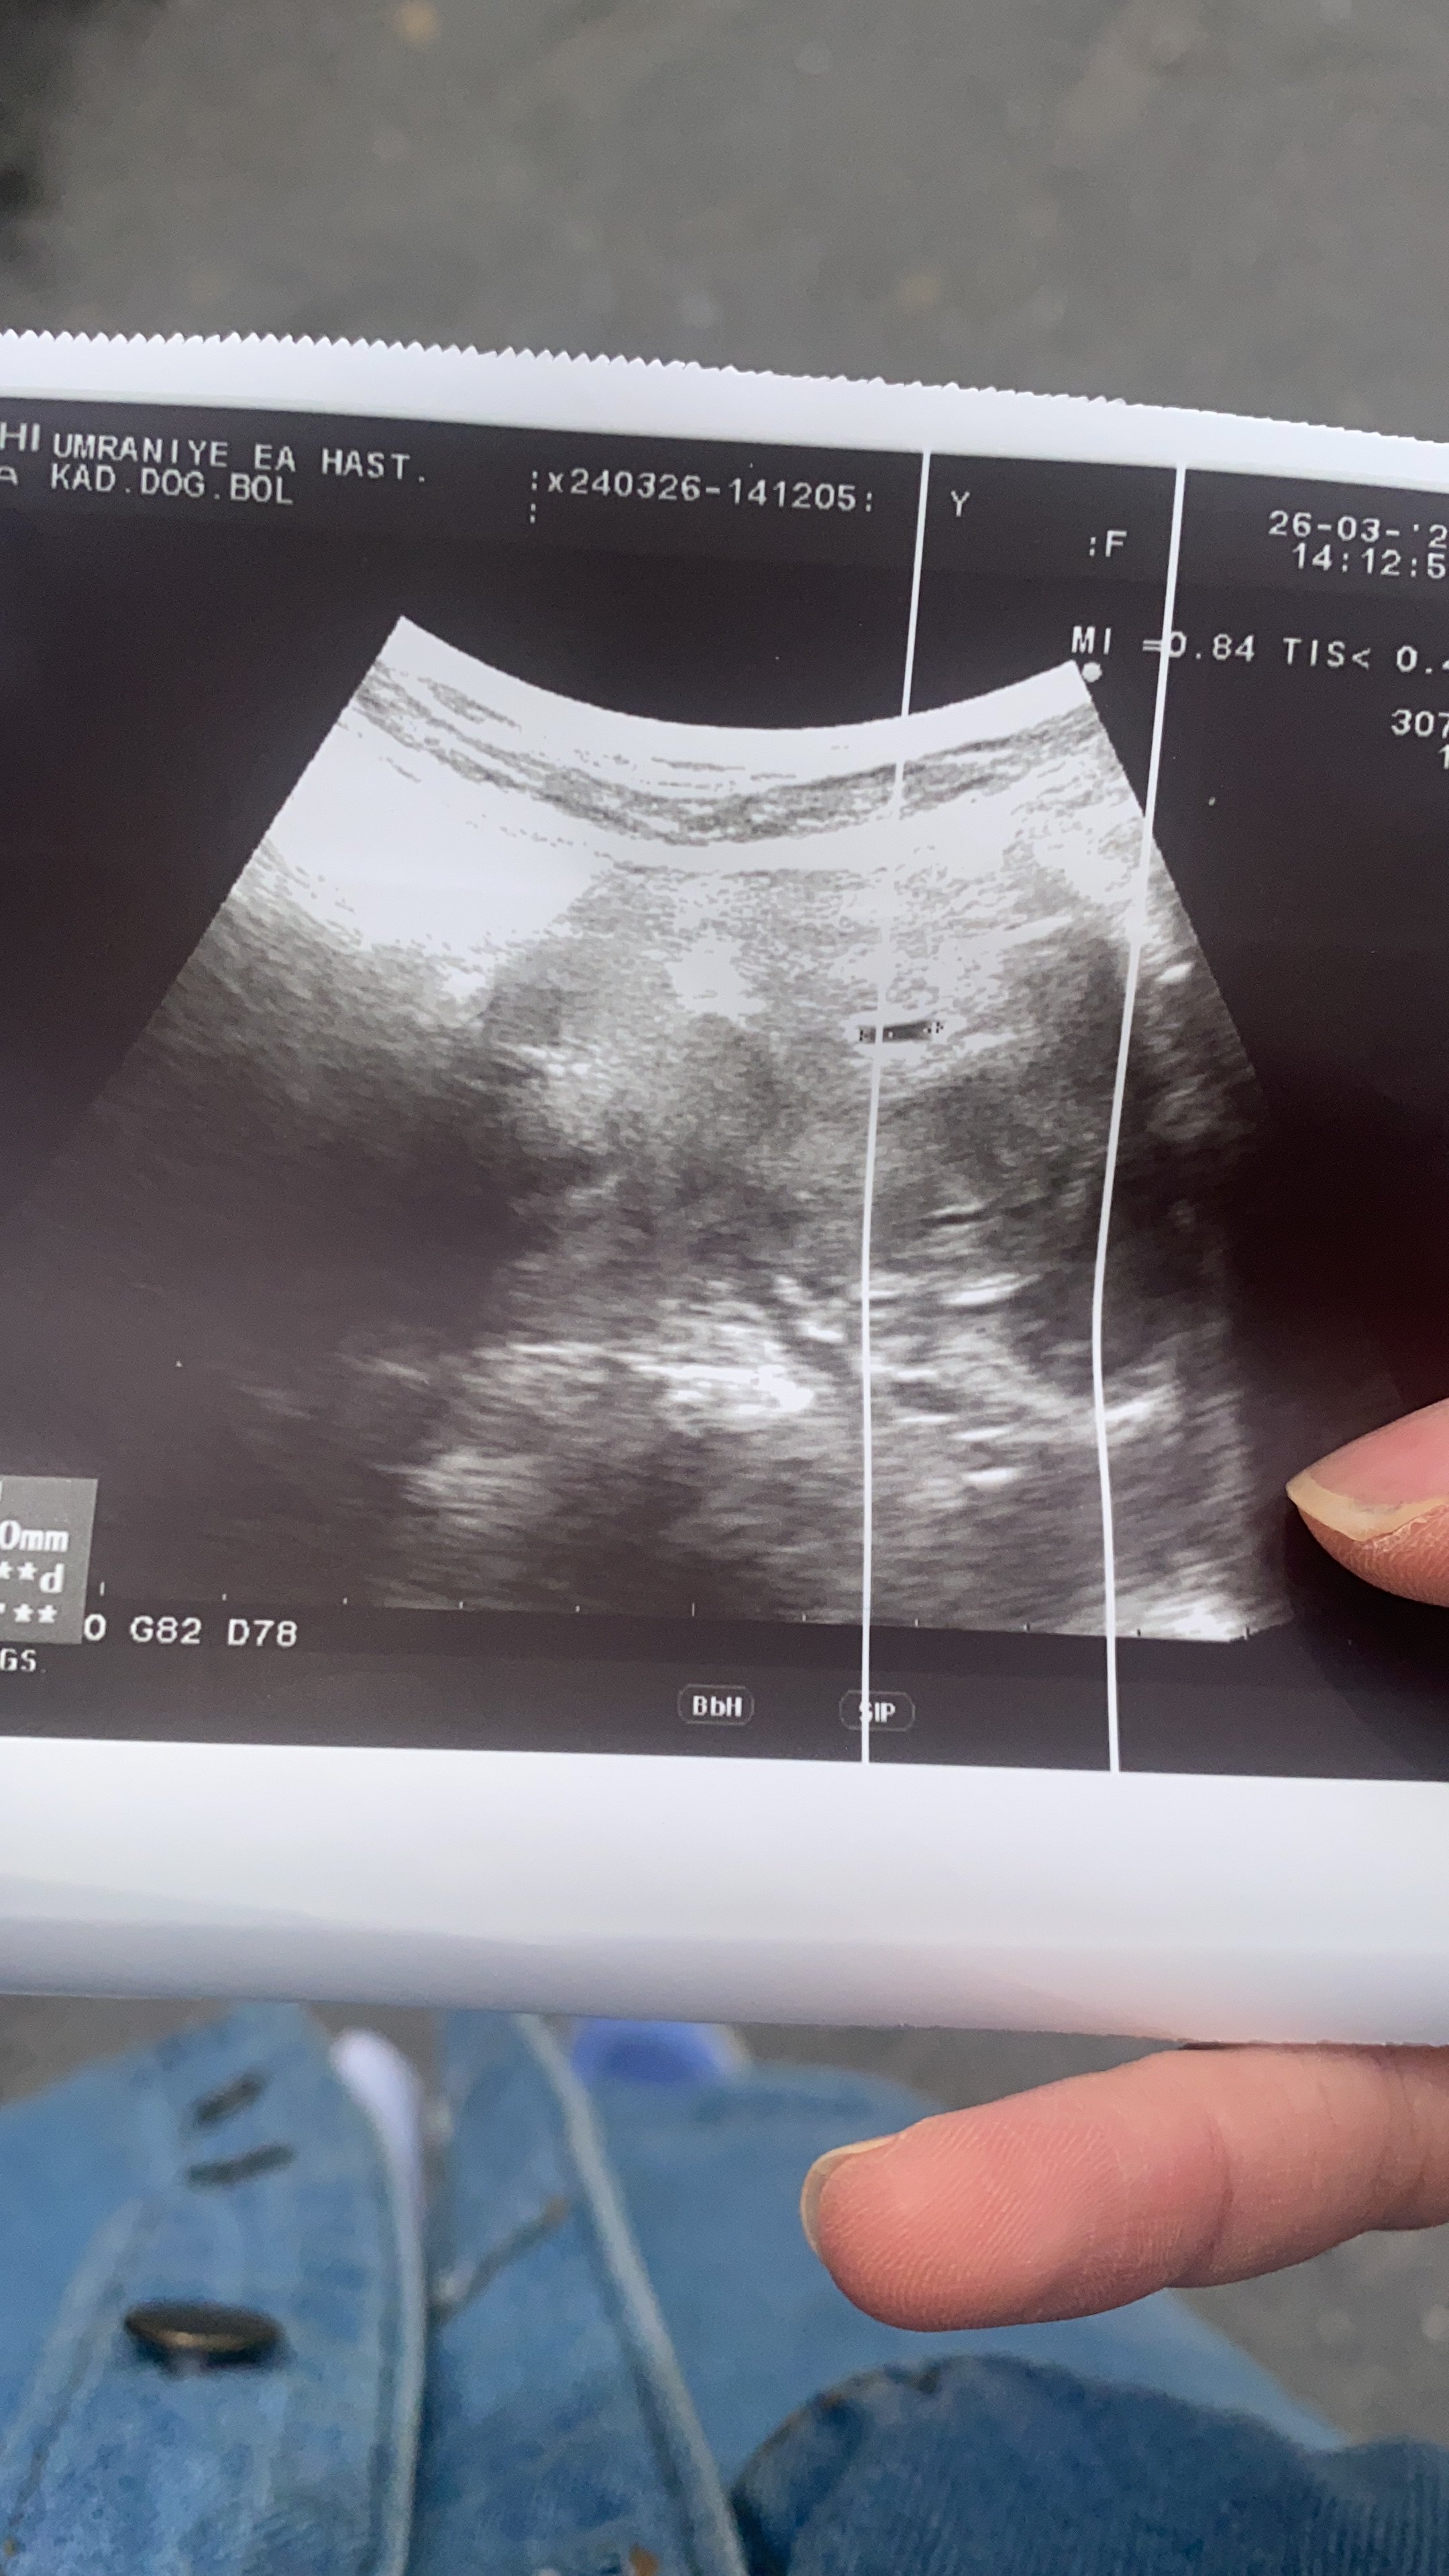

Merhaba 6 haftalık gebeyim 11 mart da doktora gittim kese gözükmedi bugün yine gittim kese gözüktü ama bebek gözükmedi ne yapmam lazım

Böyle bişey çıktı ama gebelikte sorun olur mu

Canım ıgg değerleri daha önceki enfeksiyonları gösterir genelde. Ve doktorunuza gitmenizi öneririm. Doktorun en sağlıklı bilgiyi verir. Toksoplazma da çiğ ve az pişmiş etten kedi dışkısından filan bulaşan bir enfeksiyon. Ciddi ya da değil demek benim diyebileceğim bişey değil ama doktora gitmen ve sonuçlarını göstermeni öneririm